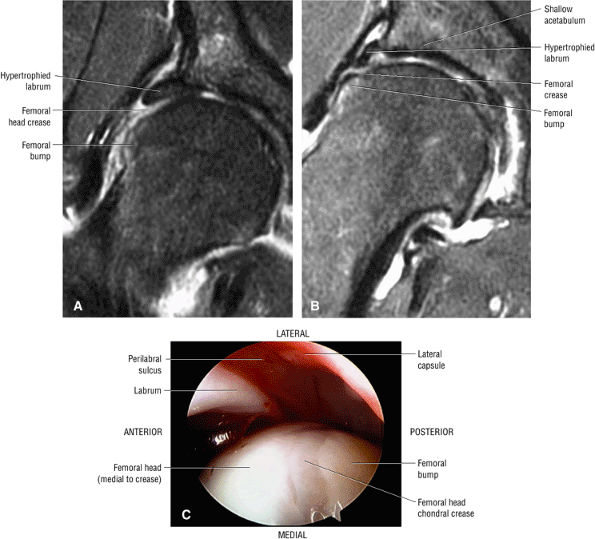

In DDH the labrum may be hypertrophic and associated with a femoral head chondral crease.

An anterosuperior cleft (Fig. 3.61) may be seen as a normal variant in the presence of a normal lateral acetabular labrum. On anterior coronal or sagittal images, this cleft is seen as a partial undercutting of the labrum on a single image. The extension of fluid into this cleft occurs from the femoral side. It may be more commonly seen in labral hypertrophy associated with mild developmental dysplasia of the hip (DDH).

An enlarged or hypertrophied labrum may occur in patients with mild DDH.17 We have observed a femoral head chondral crease (Fig. 3.66) in these patients, creating a demarcation trough medial to a femoral head bump immediately proximal to the physeal scar. Patients who demonstrate femoroacetabular impingement (or lateral acetabular rim syndrome in DDH) also have direct impingement between the lateral acetabular labrum and the femoral head.

FIGURE 3.66 ● Femoral head chondral crease with adjacent bump proximal to the physis in a mild DDH case with a hypertrophied labrum. (A) A mild crease is shown on this coronal FS PD FSE image. (B) This coronal FS PD FSE image shows a prominent femoral head crease secondary to impingement between the hypertrophied labrum and the articular surface of the lateral femoral head proximal to the physeal scar in another DDH patient. (C) Arthroscopic view of femoral head crease demarcating the femoral head articular cartilage medially from the lateral bump. The crease or cleft is opposite the lateral edge of the hypertrophied labrum. The normal perilabral sulcus is also shown between the labrum and capsule.